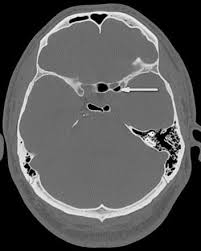

Sphenoethmoidal Air Cell Radiology Reference Article Radiopaedia Org Radiology Cell Internal Carotid Artery